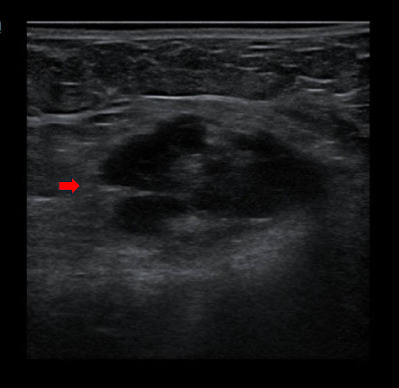

Abdominal wall endometriosis (AWE) is a rare type of endometriosis, with an incidence ranging from 0.1% to 0.4%. It requires a high index of suspicion to avoid delays in diagnosis and treatment. This case is rather special because AWE occurred without a history of abdominal surgery or pelvic endometriosis. Herein, we report the case of a 48-year-old para-3 woman with localised cyclical abdominal pain associated with abdominal distension. On assessment during menstruation, there were localised tenderness at the right suprapubic area and a non-tender suprapubic mass corresponding to a 14-week-sized gravid uterus. An ultrasound revealed the presence of a heterogeneous hypoechoic lesion at the subcutaneous layer of the right suprapubic region sized 1.8×3.2×4.4 cm with poor demarcation. There were also multiple uterine fibroids varying in size and location. She underwent exploratory laparotomy, total abdominal hysterectomy with bilateral salpingo-oophorectomy and abdominal wall mass resection. Intraoperatively, the right abdominal wall mass measuring 6x5 cm and involving the subcutaneous layer was found to adhere to the rectus sheath with some chocolate-stained areas without connection to the peritoneal cavity. Additionally, multiple uterine fibroids were noted. There was no pelvic endometriosis, and the other pelvic organs were normal. The histopathological diagnosis of the abdominal wall mass was endometriosis. AWE should be one of the differential diagnoses even in the absence of previous surgery when encountering a patient with an abdominal wall mass especially when it is related to the menstrual cycle.